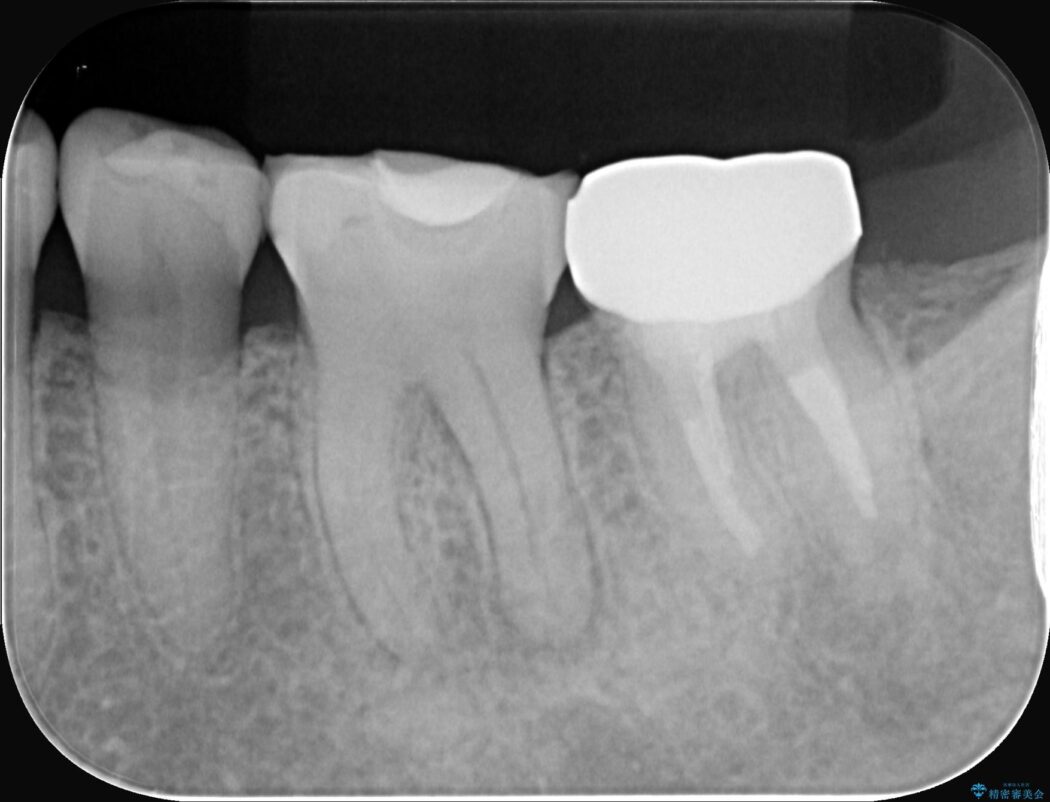

レントゲンを確認すると、歯髄腔が狭くなり根管が石灰化している難症例でした。

患者様の大切な歯を残すため、歯科用顕微鏡を用いた精密根管治療を行うことで、狭く、見えにくい根管を正確に探し出し、治療を完了させる計画を立案しました。